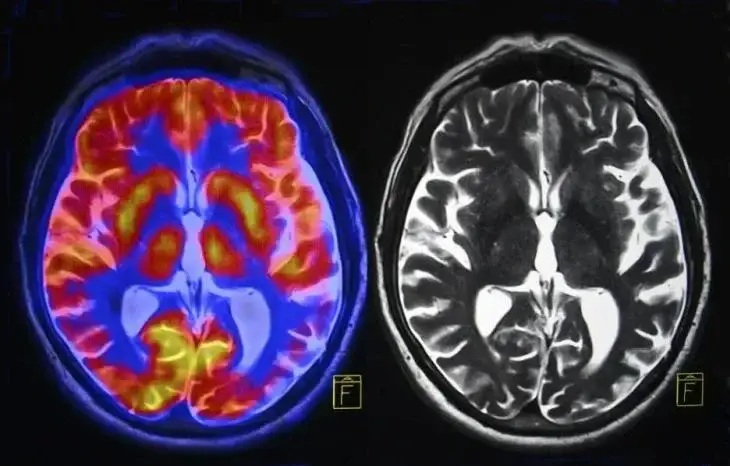

Изследователи от Националните здравни институти в САЩ публикуваха нови данни в списанието Alzheimer's & Dementia, които разкриват, че спазването на средиземноморската диета може да подобри мозъчната функция и да забави когнитивния спад, особено с напредване на възрастта.

Участниците, които стриктно спазвали средиземноморската диета, показали най-нисък риск от когнитивно увреждане.

- Фокус върху риба и зеленчуци: Те имали най-силен защитен ефект върху мозъчната функция.

Доброволци с гена ApoE, свързан с повишен риск от болестта на Алцхаймер, също показали значителен спад в когнитивните функции. Въпреки това, спазването на средиземноморската диета компенсирало до голяма степен негативното влияние на генетичния фактор.

Средиземноморската диета предлага надежден начин за забавяне на стареенето на нервната система и намаляване на риска от деменция. Този подход, базиран на богати на хранителни вещества храни и ограничаване на вредните продукти, е ефективен инструмент за поддържане на когнитивното здраве дори при наличието на генетични рискове.